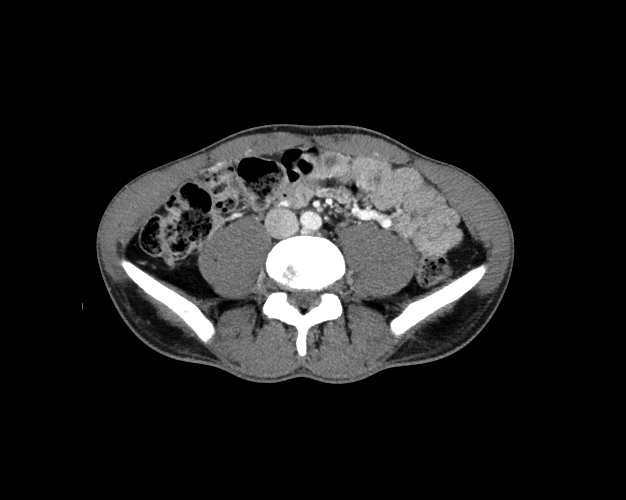

Body

Covers abdominal CT anatomy.